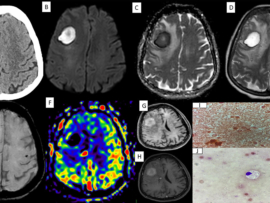

A 5-year-old male child presented with complaints of recurrent generalized tonic–clonic seizures and right-sided weakness ,predominantly involving the lower limb along with anger outbursts and abnormal behaviour.